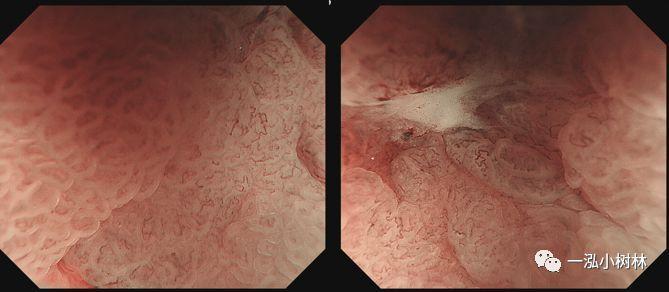

例1 胃窦病变

图1c NBI高倍放大:IMVP(+)、IMSP(+)、DL (+)